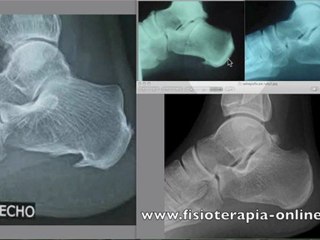

Condromalacia rotuliana. Signos radiológicos.

Visita - Todo sobre fisioterapia.br Muestro los signos radiologicos mas comunes en las radiografias de la rodilla en el caso de la condromalacia rotuliana.br Es la parte mas importante en el diagnostico de la condromalacia rotuliana.